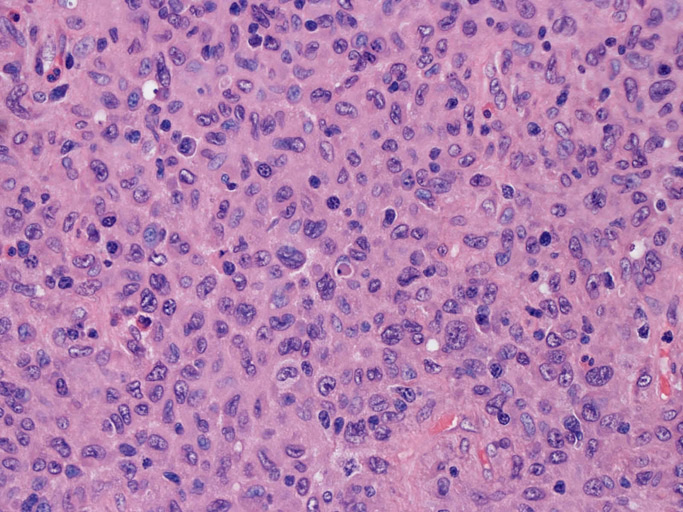

大型細胞の増殖よりなる腫瘍。縦溝,しわ,切れ込みのある核をもった大型細胞も出現する。クロマチンは顆粒状で核小体も明瞭である。核分裂は >50/10hpfと多い。eosinophilsは少ない。壊死が多発することがある。未分化ないし低分化な細胞像, 組織所見のため鑑別診断は多岐にわたり、的確な免疫染色を行う必要がある。

皮膚に異型細胞の浸潤がみられる。異型細胞は表皮内に浸潤するほか、表皮真皮境界部, 真皮, 皮下脂肪組織にもびまん, 結節様の浸潤所見を示す。血管周囲に浸潤、集蔟する所見も多く見られる。 増殖浸潤細胞の核には類円形や腎臓形, またはへこみ, 切れ込み, 溝などを有する多型な核が認められる。クロマチンは粗でvesicularな核が多い。核小体の明らかな核もある。好エオジン性の核内封入体様構造も少数に見られた。mitosisは容易に認められる。hyperchromaticな多型核, bizzarreな細胞が高頻度に認められ異型度は高いと考えられる。細胞質は境界不明瞭, 淡明または泡沫様の 好エオジン性胞体である。